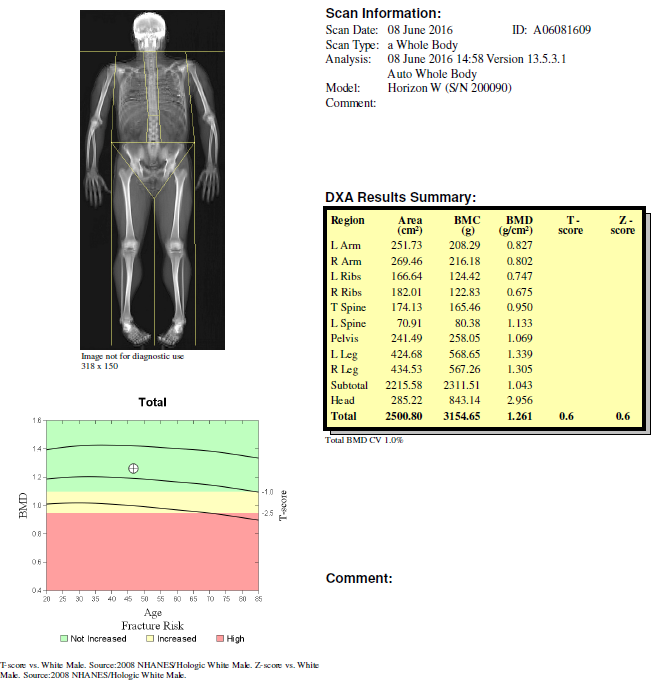

This tool can be used to accurately estimate body fat, lean body (muscle) mass, and bone mineral density.

Results outlining the amount and location of muscle and fat mass of the whole body and each appendage

Finally, Dexa Scan also outlines the health status of your bone’s, via an estimation of your bone mineral density. Early detection of a loss of bone mineral density is important in preventing osteoporosis and osteopenia (deficient bone mineral density). Dietary and training interventions can be tailored to overcome these related declines in bone health. In non-load baring sports, such as cycling, bone mineral density can often be lacking. Simple weight baring activity and exercise, such as GYM, along with dietary interventions (if insufficient) can assist in stabilizing this decline.